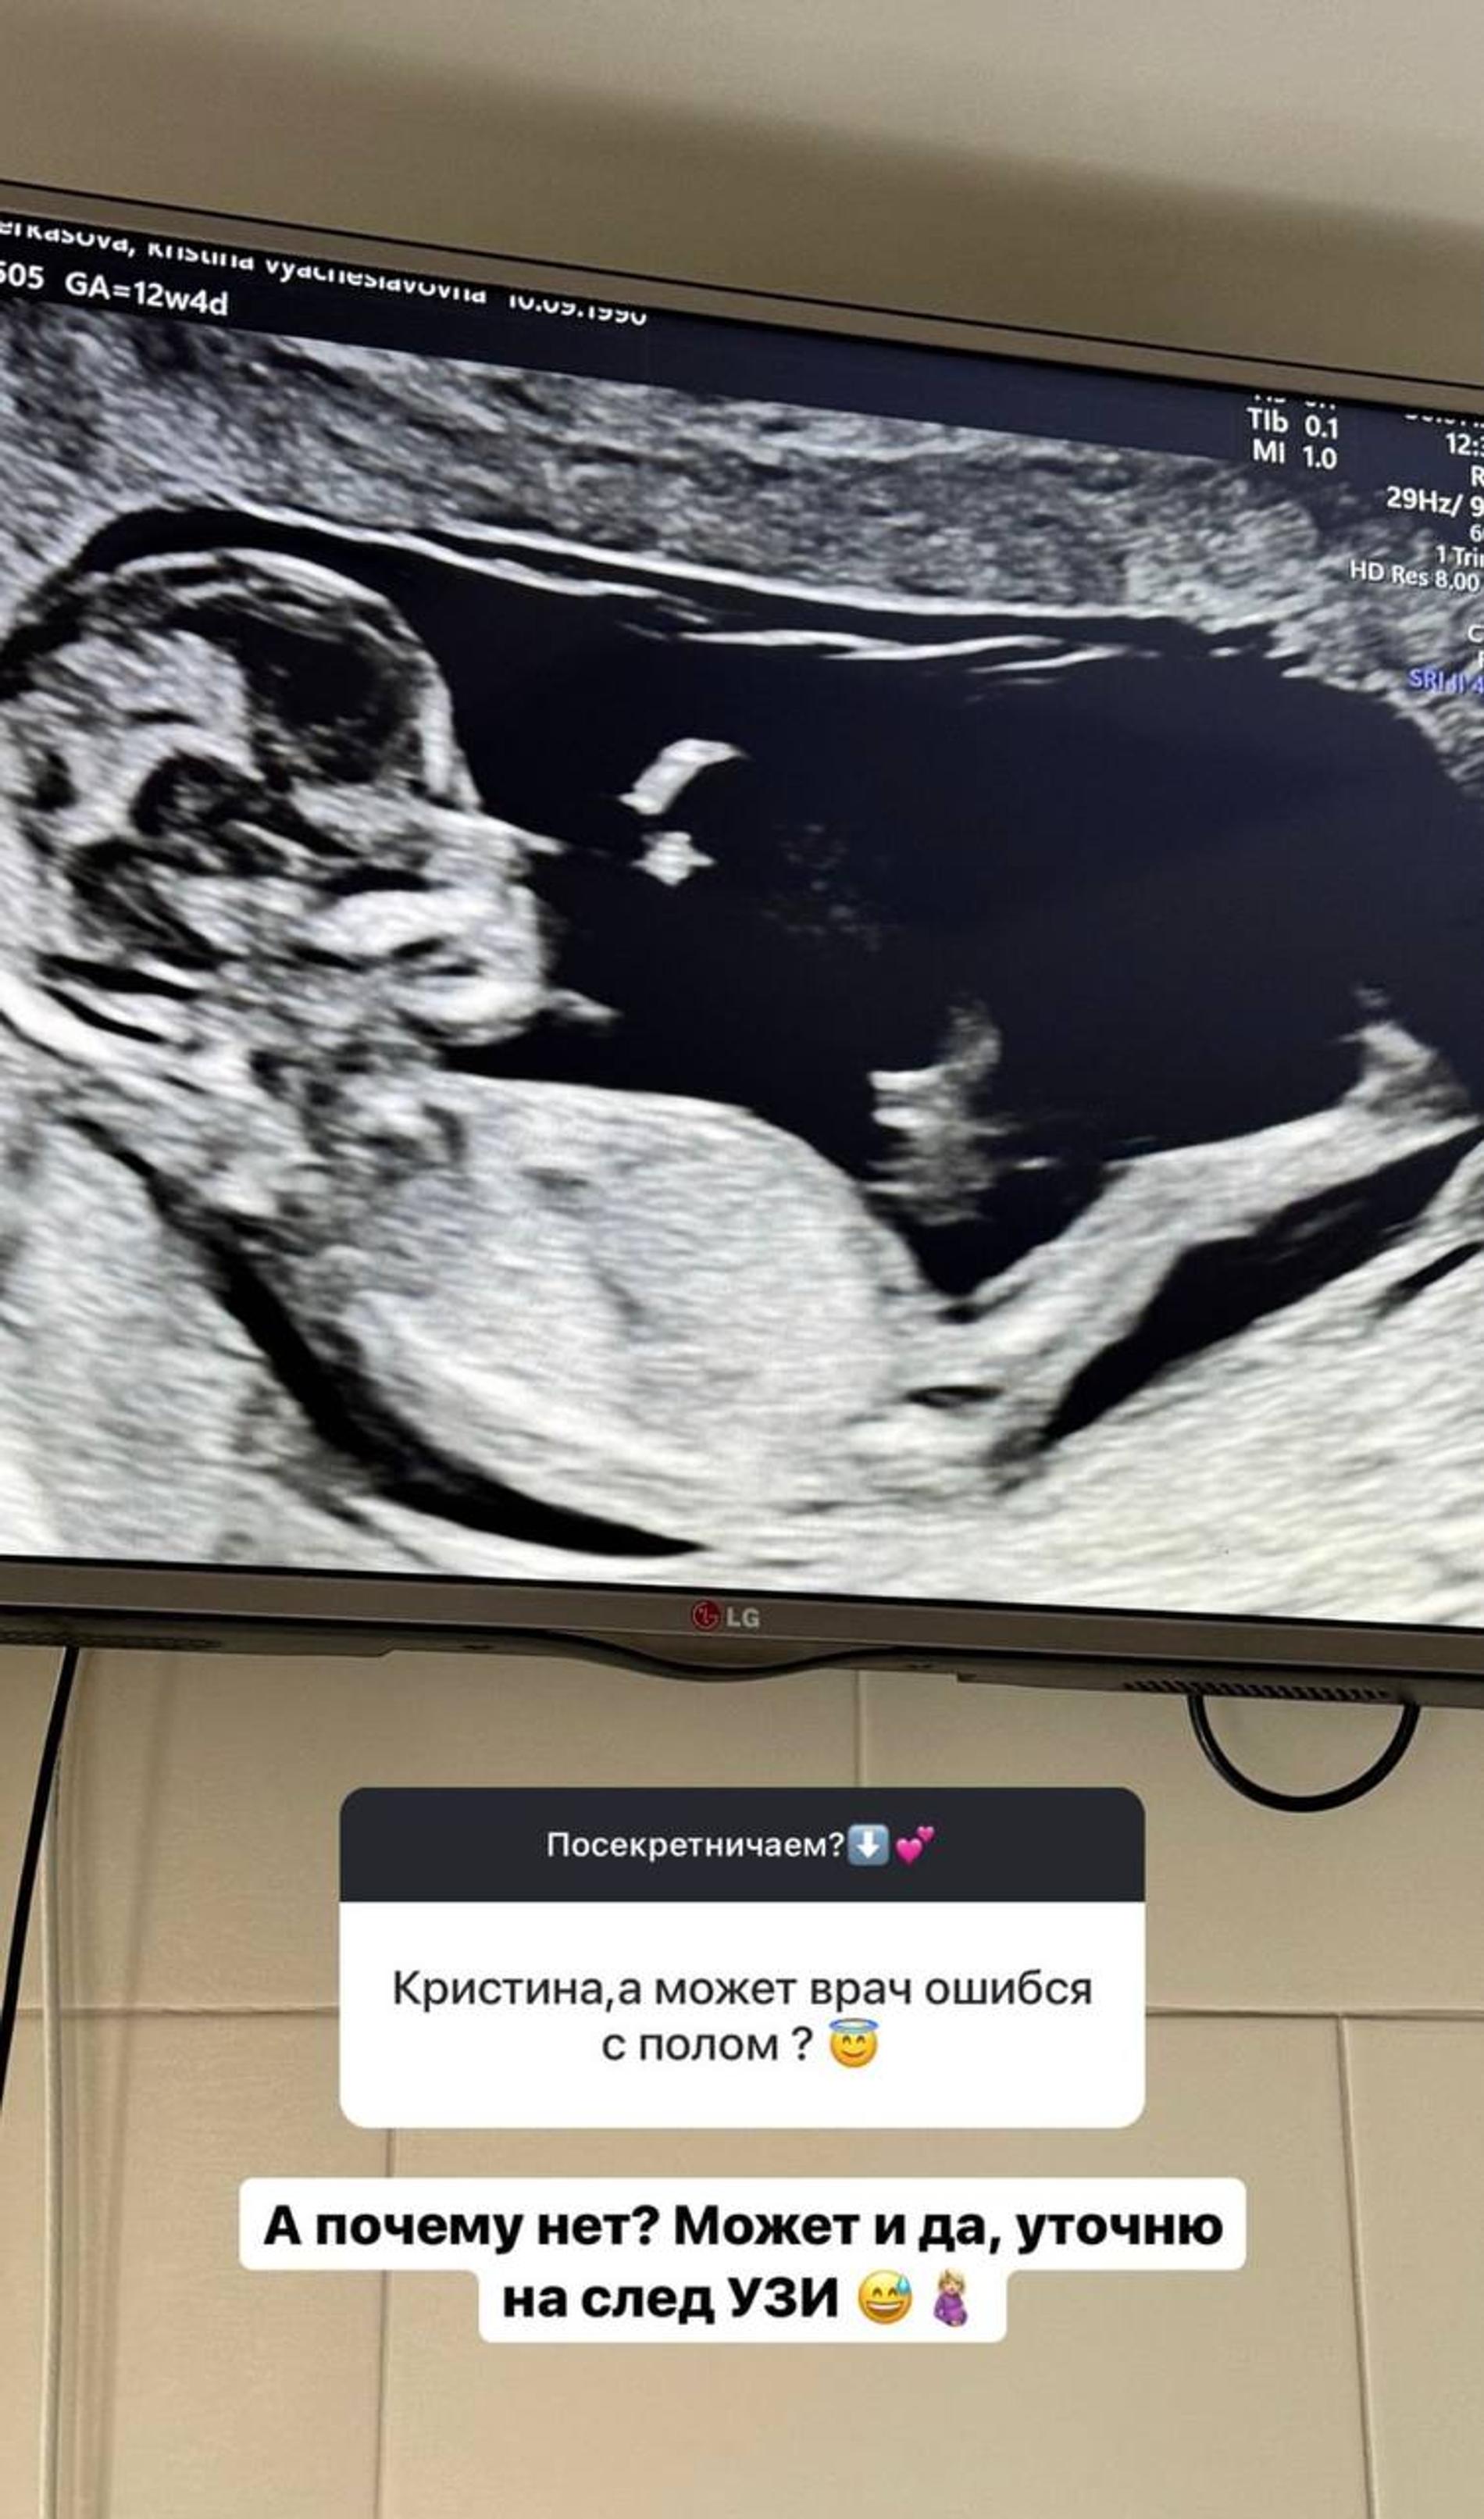

На днях Кристина и Андрей Черкасовы поделились роликом с гендер-пати. Реакция на пол ребенка у супругов оказалась неоднозначной: влюбленные мечтали о девочке, но станут родителями еще одного мальчика. Девушка честно написала, что в шоке настолько, что хочет перепроверить информацию во время следующего УЗИ. Оттого публика и набросилась на звезду «Дома-2» из-за якобы неискренности. «У вас на лице было написано полное разочарование. Ужас», — написал ей фолловер.

Кристину комментарий задел. В доказательство своего удивления она прикрепила кадры, на которых они с Андреем чуть ли не плачут от счастья. «Как хочется послать на три буквы таких неприятных дамочек», — не сдержалась девушка. Как бы там ни было, она допускает, что врач мог ошибиться с полом ребенка — все признаки указывали на то, что у пары родится девочка.